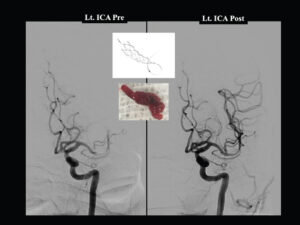

Example- A gentleman presented with transient Rt. side facial Paralysis due to more than 95 % blockage of Neck Artery. After removal of blockage by STENTING , he never had these episodes.

More than 70%- 90% blockage of Brain Arteries cause Paralysis due to ‘TRANSIENT’ lack of blood supply to Brain .

In this situation by Interventional Neuroradiology techniques BLOCKAGE can be opened and Normal blood flow to brain will be restored .

Example- BLOCKAGE A gentleman presented with transient Rt. side facial Paralysis due to more than 95 % blockage of Brain Artery. After removal of blockage by STENTING , he never had these episodes.